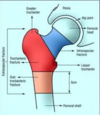

Label the components of the pelvis and femur